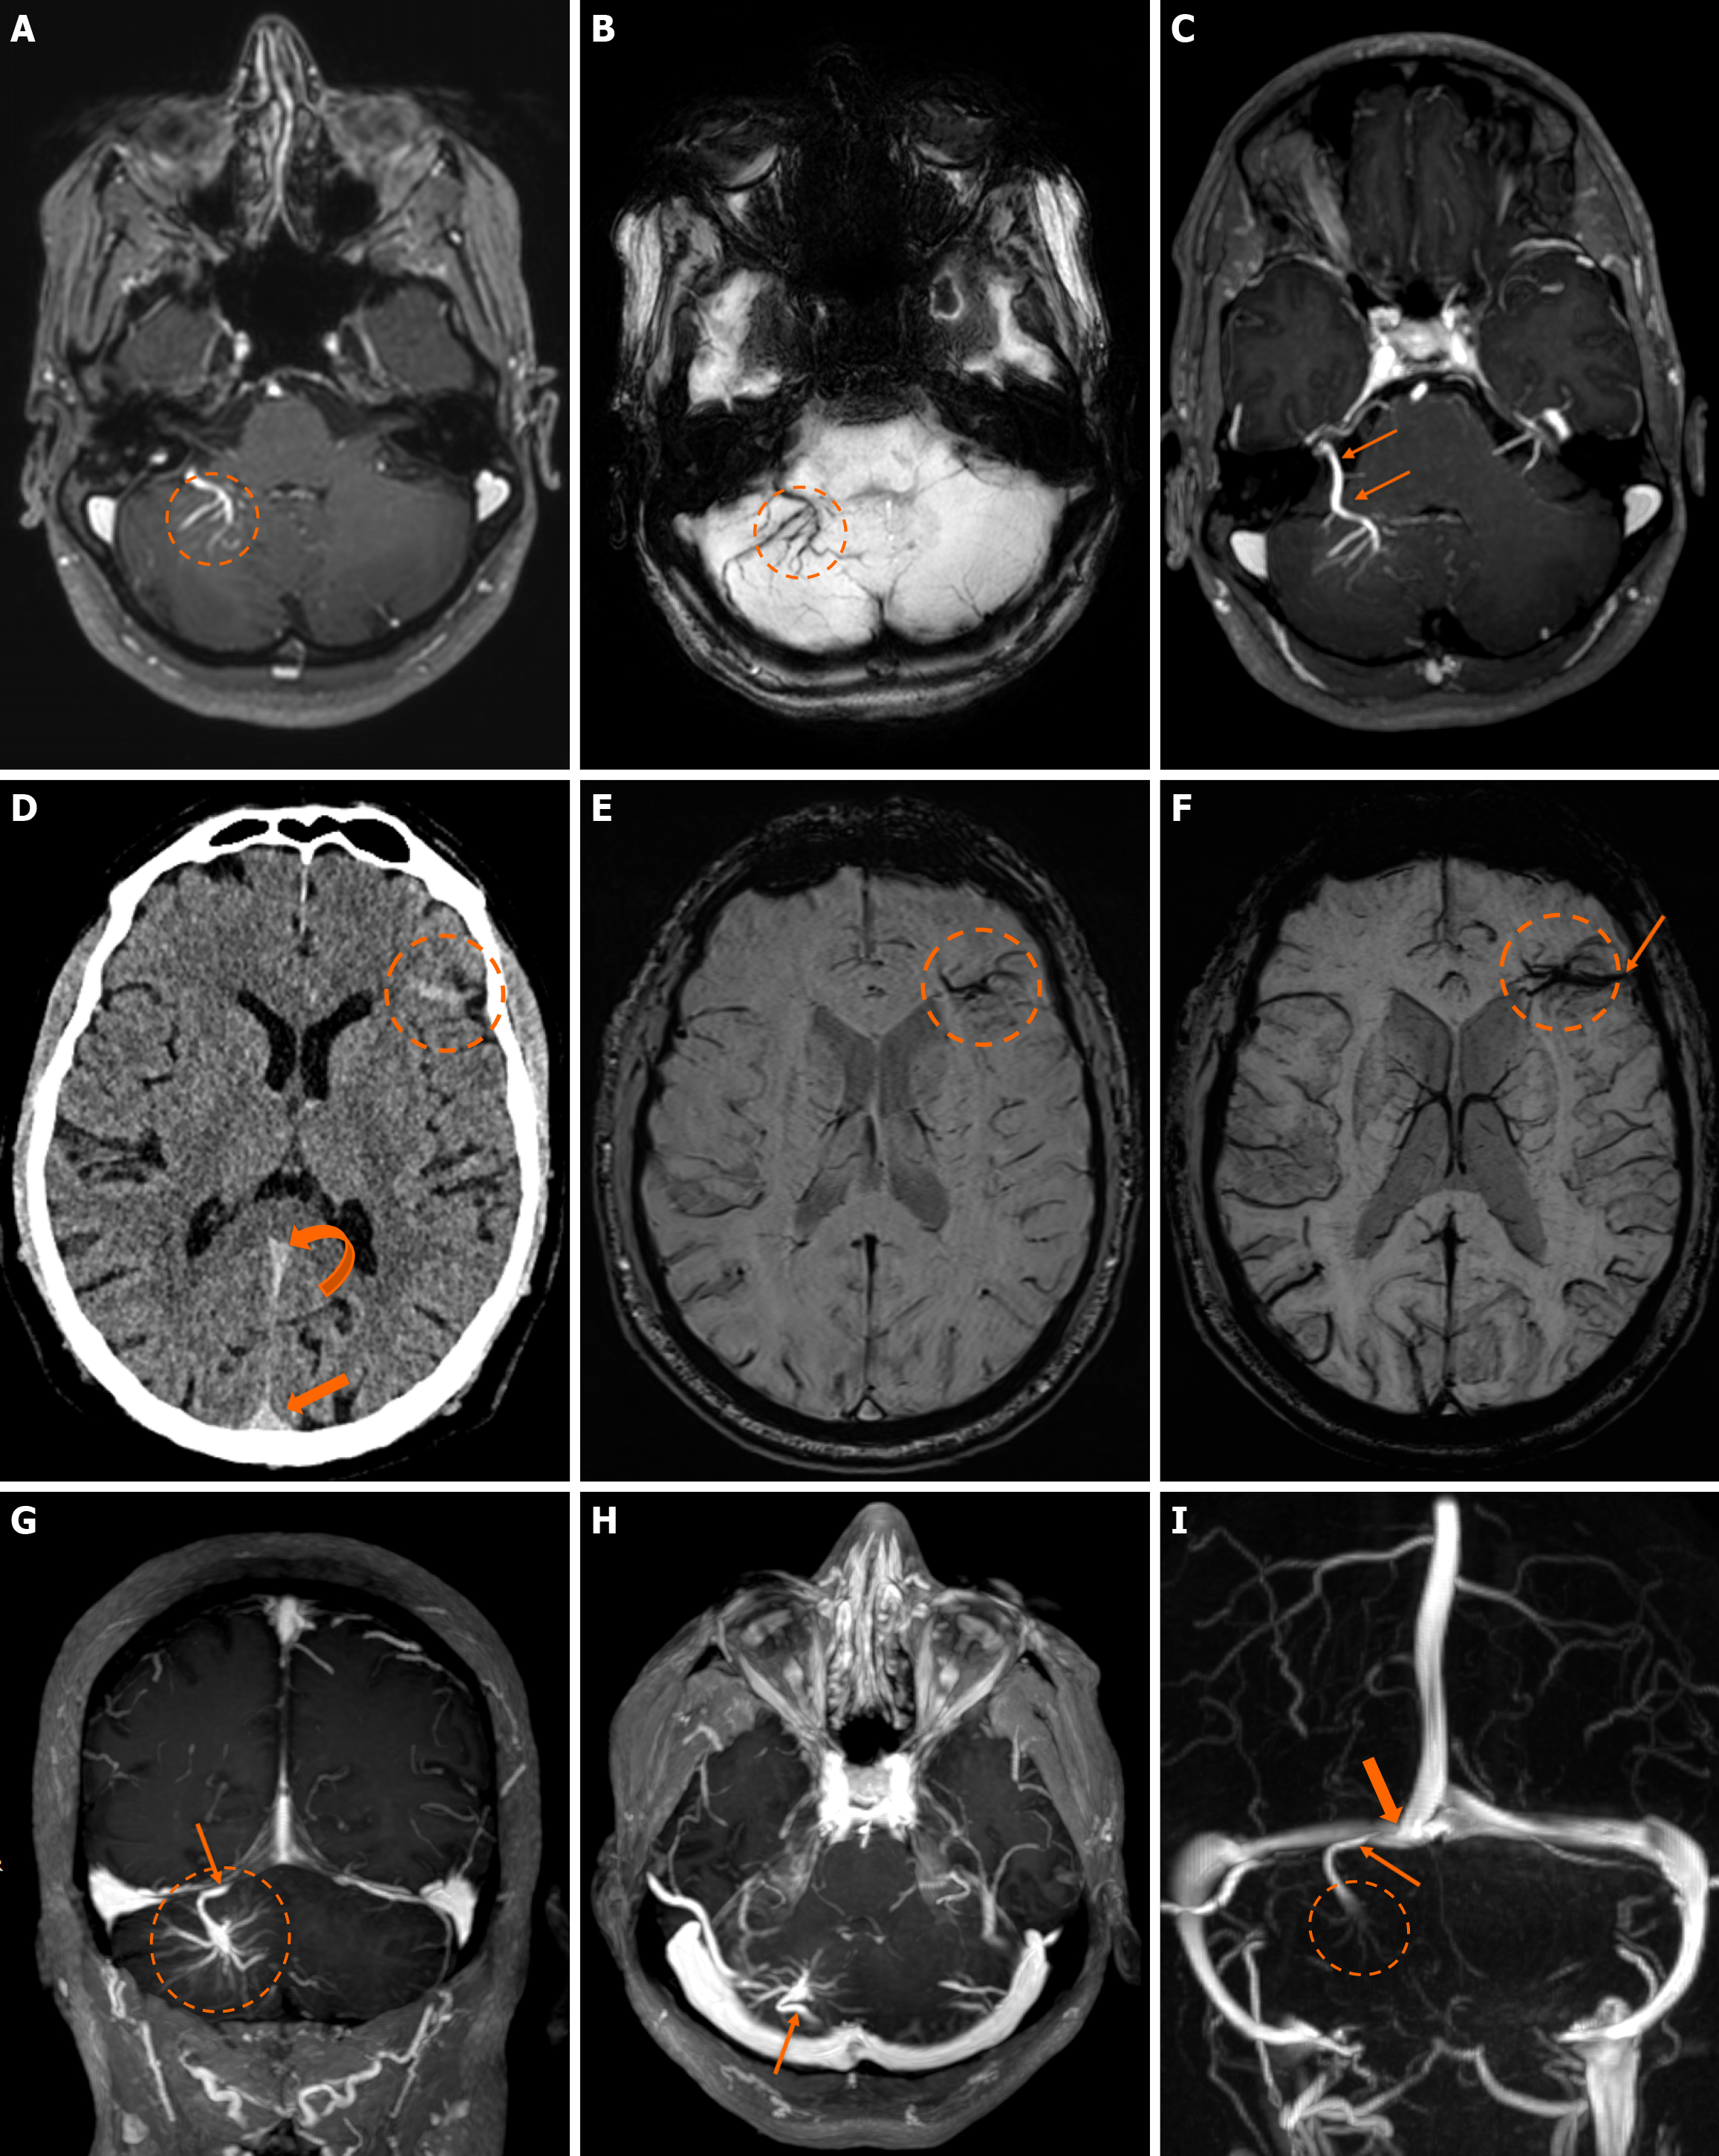

Imaging findings in coexistent DVAs and CMs will be the combination of those described for each malformation separately. Awareness of the possibility of their coexistence may prove invaluable in clinical practice. This is because recognition of a DVA close to a brain hemorrhage may raise suspicion for an underlying CM as the most likely etiology. Additional examinations and follow-up imaging following hematoma resolution will further enhance diagnostic confidence. Figures 8, 9, 10 and 11 illustrate clinical examples in which identifying the synchronous presence of a DVA adjacent to a brain hemorrhage (or suspected brain hemorrhage) enabled the diagnosis of a probable underlying CM as the most likely etiology, thereby avoiding unnecessary examinations or interventions.

The clinical applicability of the Zabramski classification is still being investigated. A retrospective cohort study evaluating the imaging evolution and clinical trajectory of 255 untreated patients with sporadic CMs over a follow-up period of approximately five years provided evidence that the Zabramski classification may facilitate risk stratification and contribute to treatment planning, particularly in determining the necessity for surgical intervention[89]. Furthermore, a recent study by Saari et al[88] established an association between the radiological characteristics of the Zabramski classification and their clinical relevance, emphasizing that type I lesions have a higher likelihood of becoming symptomatic. Nikoubashman et al[90] suggested an additional category (type V lesions) accounting for cavernomas presenting with gross extralesional hemorrhage. Various examples of CMs on CTs and MRIs, including familial cerebral CM cases, are shown in Figures 4, 5 and 6.

The presence of T1 hyperintensity within perilesional edema surrounding a hemorrhagic lesion has proven to be a valuable diagnostic feature, aiding in the differentiation of CMs from other hemorrhagic lesions[92]. The same authors also reported a significantly higher occurrence of the hypointense signal or rim on T2-weighted images in CMs compared to neoplastic lesions[92]. In cases where CMs occur in atypical locations, such as the cavernous sinus or extraaxial regions, the differential diagnosis becomes more complex, as these lesions may mimic other vascular, neoplastic, or inflammatory lesions, necessitating careful imaging interpretation and, in some cases, additional diagnostic workup. In addition, identifying a DVA within the vicinity of a hemorrhagic brain lesion may strongly suggest an underlying CM as the incriminating etiology, further representing a clue that can assist in the differential diagnosis approach.